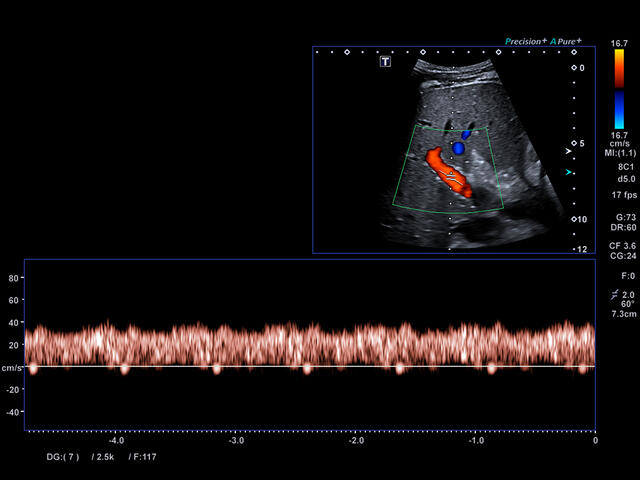

Aplio a550 может работать с линейным матричным датчиком и поддерживает новейшие монокристаллические датчики. Также Aplio a550 поддерживает большое количество дополнительных опций, таких как - SMI, Компрессионная эластография, Эластография сдвижной волны, Smart Fusion, исследования с использованием контраста (CEUS), 3D реконструкции в реальном времени (4D), функции автоматической оценки подвижности миокарда и фракции выброса.

- SMI. Опция, упрощающая визуализацию микроциркуляторного русла. С ее помощью обследуются сосуды с низкой интенсивностью кровотока, изучаются наиболее тонкие структуры. SMI упрощает диагностику новообразований, минимизирует вероятность ошибки.

CDI-Режим - Цветной допплер

Уровень сосудистой визуализации SMI в сочетании с высокой частотой кадров повышает диагностическую достоверность при оценке поражений, кист и опухолей.

SMI с цветовой кодировкой позволяет одновременно отображать информацию о потоках и оттенках серого с высокой временной и пространственной информацией.